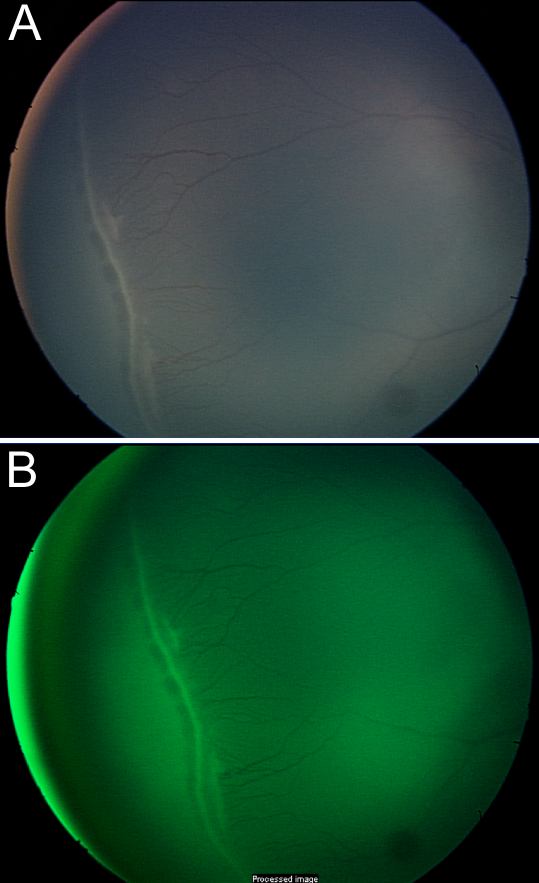

Figure 13. Digital fundus photographs of ROP

A: Original digital fundus photograph of ROP. B: The original image was enhanced by increasing contrast, subtracting the red and a little blue for better appreciation of the ridge and retinal blood vessels.